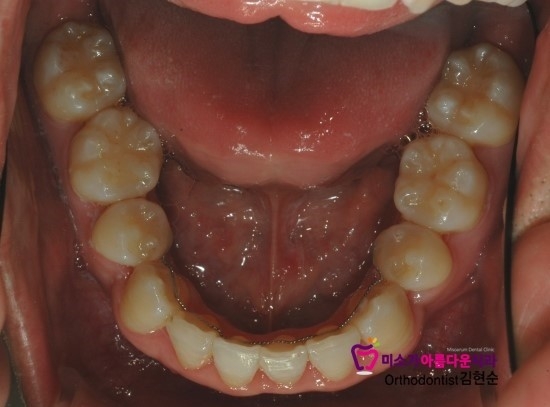

치열이 이미 심하게 뒤틀린 상태여서 공간확보를 위해

치열을 고르게 다 편 상태이고

다시 치열이 뒤틀리지 않게 이빨 안쪽으로 유지장치를 붙여드렸습니다.

고정식 교정유지장치인데

치아 안쪽에 얇은 와이어를 붙이는 것으로

보통 일,이주 정도면 이물감이 적응이 되서 교정장치의 보조적 역할을 합니다.

교정장치를 제대로 착용하지 않았을 때를 대비해서 붙여드립니다.

치아 교정을 마친 이후에도

치아가 다시 원래 자리로 돌아가려고 하기 때문에

교정유지장치는 반드시 착용해야합니다.